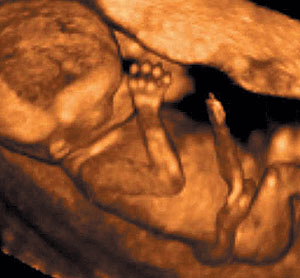

La única foto que voy a subir en este post: un feto de 12 semanas. Si no es un ser humano yo soy vegetariano.

En fin, creo que basta con usar un poco el sentido común. He visto también muchas ecografías, ecografías de cuatro semanas, de ocho semanas, de tres meses, de cinco meses... y para mi sorpresa, en todas ellas he visto un niño. Por tanto, negar que el aborto es la muerte de un ser humano es negar la ciencia, la razón y el sentido común.El aborto no es un derecho, es un sufrimiento para la mujer